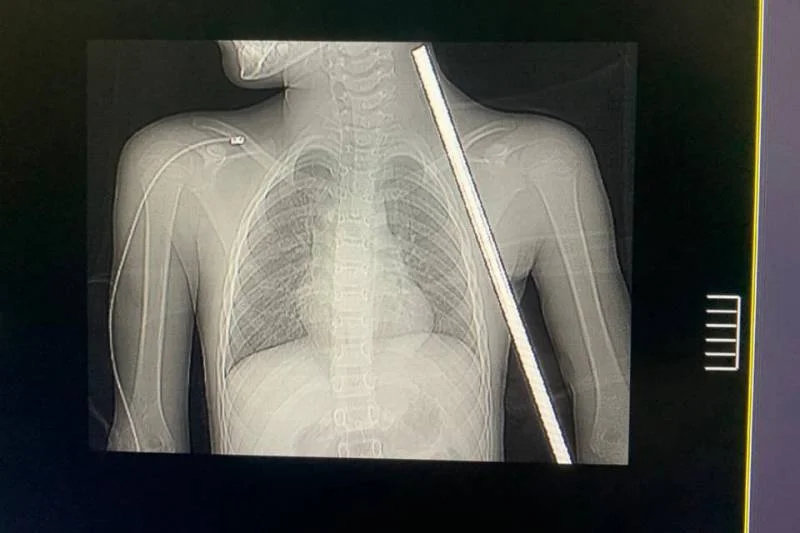

Foto: Reprodução |Um momento de descontração durante as férias quase se transformou em tragédia para Isabela da Conceição, de apenas 8 anos, no último dia 5 de janeiro, em Novo Progresso, no sudoeste do Pará. Enquanto brincava em uma mureta em um terreno baldio, Isabela sofreu um acidente impressionante: um vergalhão de ferro perfurou seu corpo, atravessando da região abaixo do tórax até próximo ao pescoço.

Segundo a neurocirurgiã Ingrid Soani, responsável pelo procedimento, o caso era extremamente delicado. “A perfuração passou muito perto de estruturas importantes, como nervos e vasos sanguíneos. Os riscos incluíam perda de movimentos nos braços, choque hipovolêmico por rompimento de vasos e infecções graves devido à ferrugem no vergalhão”, explicou.

Antes da cirurgia, a equipe médica realizou exames de imagem detalhados para mapear os danos e planejar a intervenção, minimizando possíveis complicações. A operação, que durou cerca de duas horas, foi conduzida com extremo cuidado.